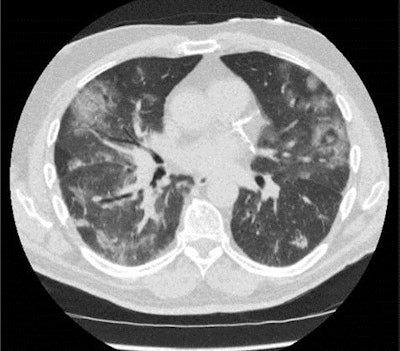

Low-dose CT shows a patient with a score of CO-RADS 5. Image courtesy of Dr. Mathias Prokop, PhD.CO-RADS encodes the suspicion of lung involvement of COVID-19 on a scale from 1 (very unlikely) to 5 (very likely) and is meant to be combined with a CT severity score that assesses the extent of pulmonary involvement. It is aimed at high-prevalence settings such as when hospital admission is considered and COVID-19 is part of the differential diagnosis.

Prokop pointed to a validation study of CO-RADS on more than 100 randomly selected cases with moderate to severe symptoms who were scanned using low-dose chest CT at the medical center. Using a positive PCR test result as the gold standard, receiver operating characteristic analysis of CO-RADS yielded an average area under the curve of more than 0.90.

"In patients presenting with moderate to severe symptoms, 20% to 50% of whom have the disease, the CO-RADS score works well," he noted. "The CT protocol requires a dose-length product of some 40 mGy-cm, which translates into an effective radiation dose of well below 1 mSv. COVID-19 can kill, so we are happy with this optimized dose."